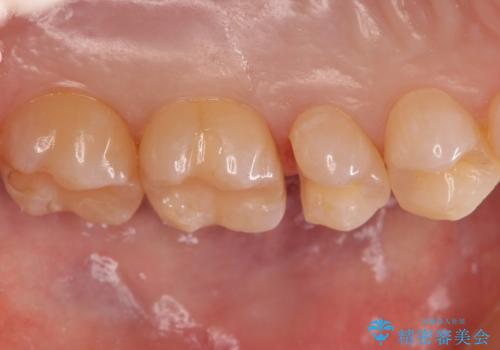

歯と歯の間の虫歯 セラミックインレーでの治療

- 検査の結果、歯と歯の間に虫歯が見つかった患者様です。

白く目立たないものでの治療をご希望されたため、セラミックインレーでの治療となりました。

歯と歯の間は虫歯の好発部位です。

適合の良いセラミックインレーで修復することで見た目の綺麗さを保ったまま治療することができます。